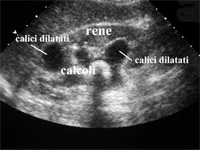

Calcolosi urinaria

La calcolosi urinaria è una patologia molto diffusa nel mondo occidentale, e in Italia in particolare. Si calcola che colpisca circa il 10% della popolazione maschile e il 5% della popolazione femminile. L'età con maggiore incidenza è quella compresa tra i 30 e i 50 anni...